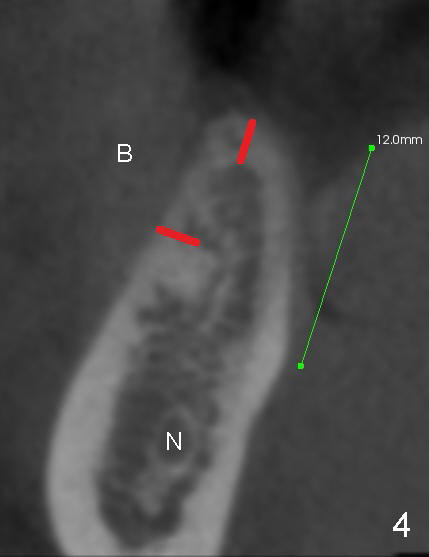

The ridge of the lower right molar is narrow buccolingually (Fig.1). After incision, ridge split is finished with a surgical fissure bur (Fig.2,3).

The patient is scheduled to return for implant placement 3 weeks later. The red lines in Fig.4 (CT coronal section) represent bony cuts in the ridge. A transverse incision is made over the top of the ridge with minimal exposure of the ridge. A curved osteotome is inserted into the upper bony cut (Fig.5). As the chisel is tapped in, the buccal segment moves buccally (Fig.6 pink arrow). When the chisel is withdrawn, a pilot drill is used to initiate osteotomy (Fig.7). As drills increase in diameter, the buccal segment continues moving buccally (Fig.8). Finally a bone-level implant (4.1 or 4.5x12 mm, Fig.9) or sub-crestal implant (4 or 4.5x8) is placed. Will the ridge split work?